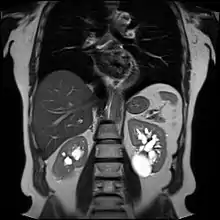

Renal cyst of the left kidney (hyperintense area) as shown on MRI.